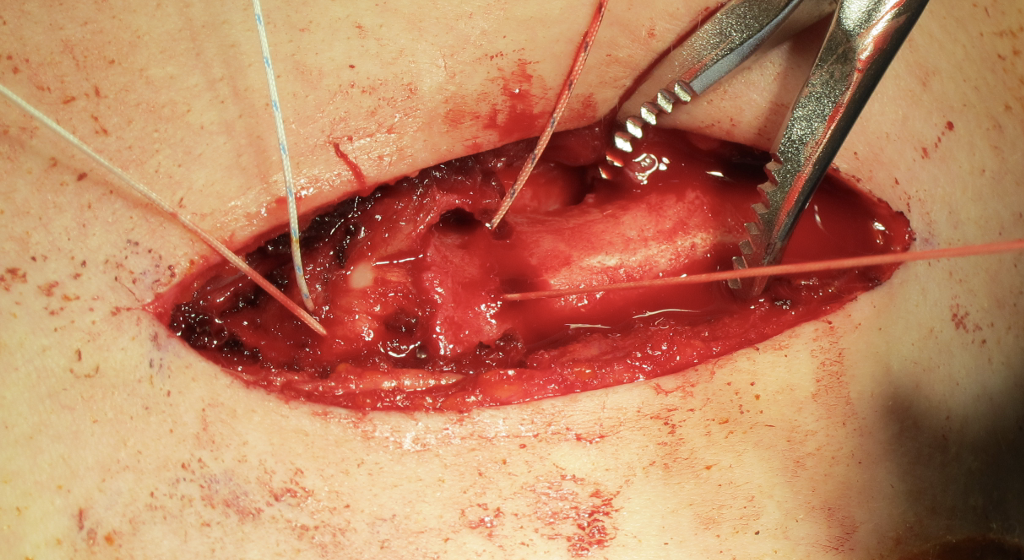

Open reduction of acute posterior sternoclavicular joint dislocation

Drill holes in manubrium and medial clavicle

Figure of 8 suture fixation